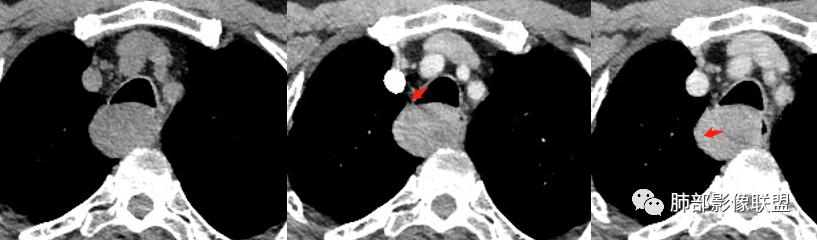

3.结合CT增强图像及食道钡餐影像(管壁整体柔软,粘膜线完整),提示肿块来源于粘膜下。

4.肿块渐进性强化,局部可见低强化区(下图红箭头所示),可以符合神经鞘瘤AB区的影像特点,尽管该部位神经鞘瘤罕见,毕竟食管壁也是有神经走行的,解剖也提示诊断的方向。

须排除的是平滑肌瘤及间质瘤。血管瘤及囊肿因强化方式不支持。